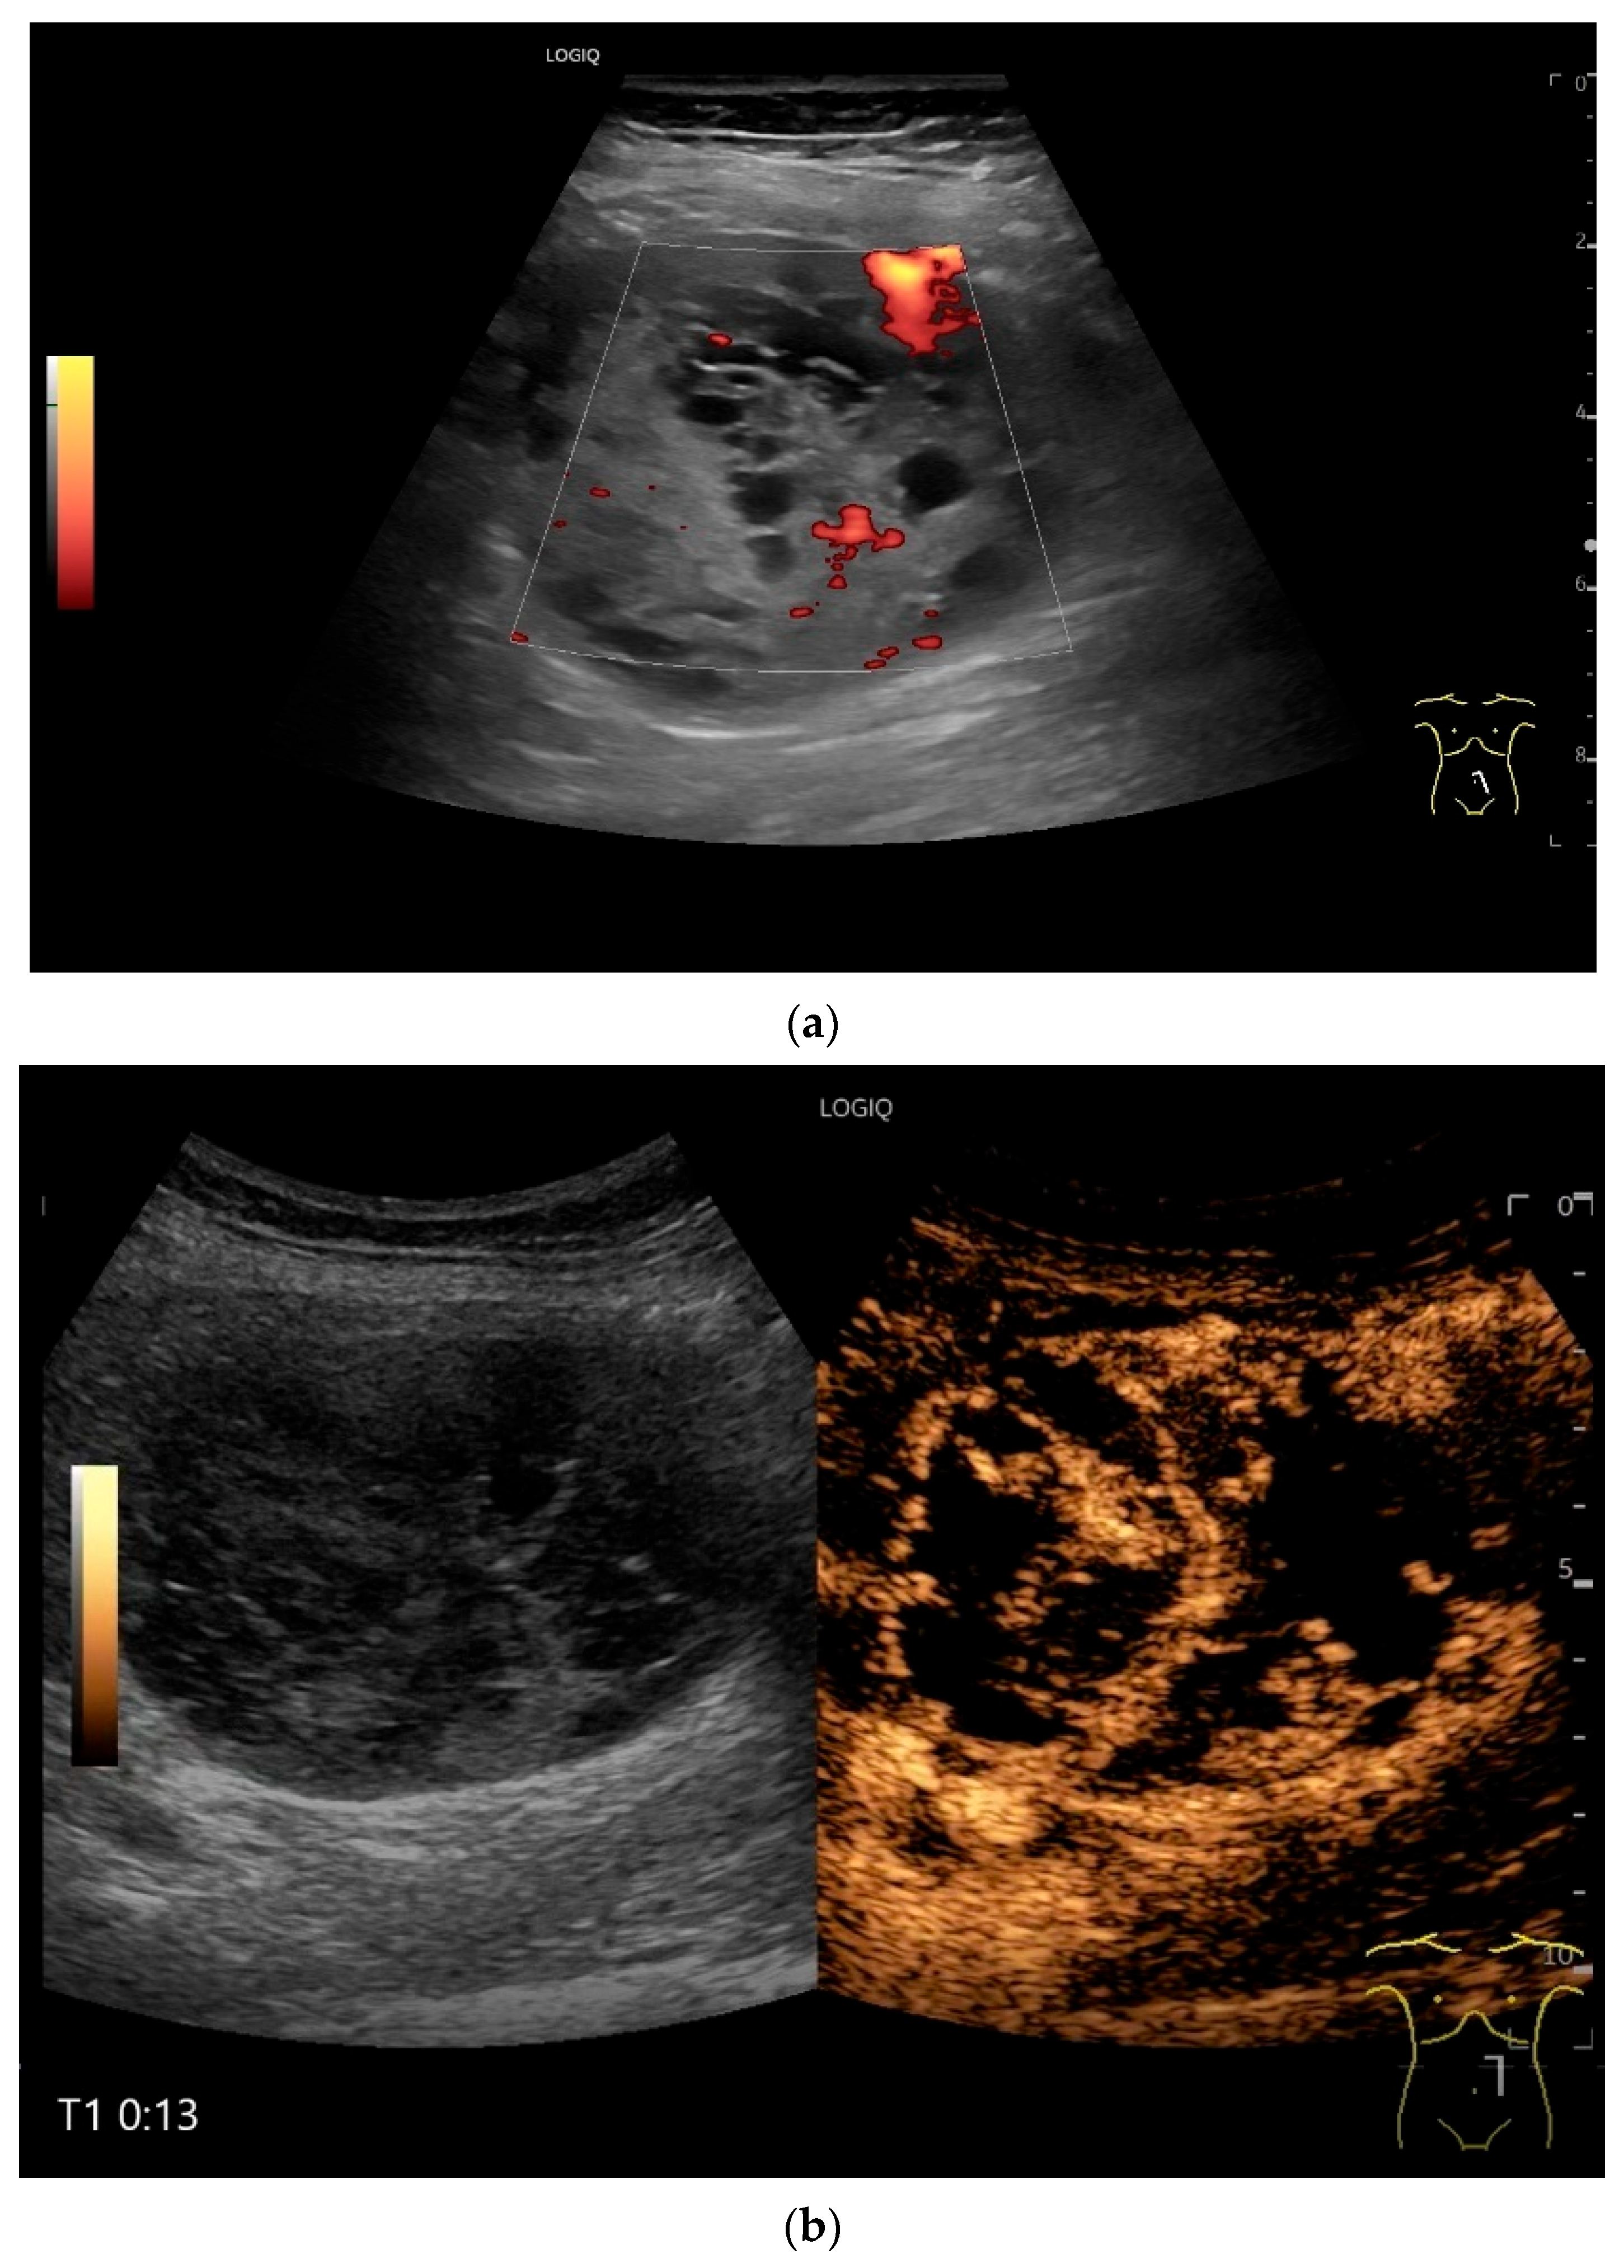

| GIST | Round hypoechoic masses, homogeneous or heterogeneous depending on size. They usually originate from the muscularis propria, which can be difficult to distinguish in US. Small vessels on CDI, hyperenhancement on CEUS. They move with the small intestine and can change position. |

- Multiparametric US, including CDI and CEUS, enhances lesion characterization by assessing vascularity and necrosis, especially in GISTs and neuroendocrine tumors.

- Sidhu, P.S.; Cantisani, V.; Dietrich, C.F.; Gilja, O.H.; Saftoiu, A.; Bartels, E.; Bertolotto, M.; Calliada, F.; Clevert, D.A.; Cosgrove, D.; et al. The EFSUMB Guidelines and Recommendations for the Clinical Practice of Contrast-Enhanced Ultrasound (CEUS) in Non-Hepatic Applications: Update 2017 (Short Version). Ultraschall Med. 2018, 39, 154–180. [Google Scholar] [CrossRef]

- Dietrich, C.F.; Averkiou, M.; Nielsen, M.B.; Barr, R.G.; Burns, P.N.; Calliada, F.; Cantisani, V.; Choi, B.; Chammas, M.C.; Clevert, D.A.; et al. How to perform Contrast-Enhanced Ultrasound (CEUS). Ultrasound Int. Open 2018, 4, E2–E15. [Google Scholar] [CrossRef]